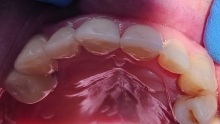

Clinica LUY ESTHETIC ART defineste parodontoza ca fiind rezultatul direct al placii dentare, care se depune pe suprafata dintilor, dar si in apropiere de marginea gingivala. Aceasta boala duce la pierderea dintilor, chiar daca ei sunt aparent sanatosi si nu prezinta carii. Edentatiile, afecteaza vorbirea, aspectul, dar si capacitatea de a mesteca.

– mobilitatea sau deplasarea dintilor;

– retractii gingivale cu expunerea radacinilor dentare;